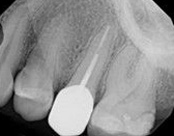

In this situation, some would say the canals are so “calcified” that root canal treatment can’t be done; or sometimes the canal can’t be found. And because of that the tooth would need an extraction and an implant. In some instances, root canal therapy can’t be done but that does not mean the tooth is a loss. The solution is micro-apical surgery, an apicoectomy.